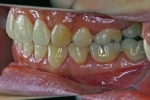

カテゴリー:ClassⅡ division 2 malocclusion (Overbite 5mm以上; 抜歯症例)

出題の意味:このケースの条件は一般の人には理解しにくいところがある。通常出っ歯というと上の前歯が外に向かっていることを想像するのが普通であるが、U1-SNが90度以下というのは、上の前歯は内側に傾いていることを示している。なんで??。つまりこれは骨格性上顎前突と考えられるもので、上顎が歯並びごと全体が前へ出ていて、それだと上下の前歯があまりにも離れてしまうため、上の前歯が内側に倒れて下の前歯と何とか接触しようとしている状態と考えられる。

| 治療中